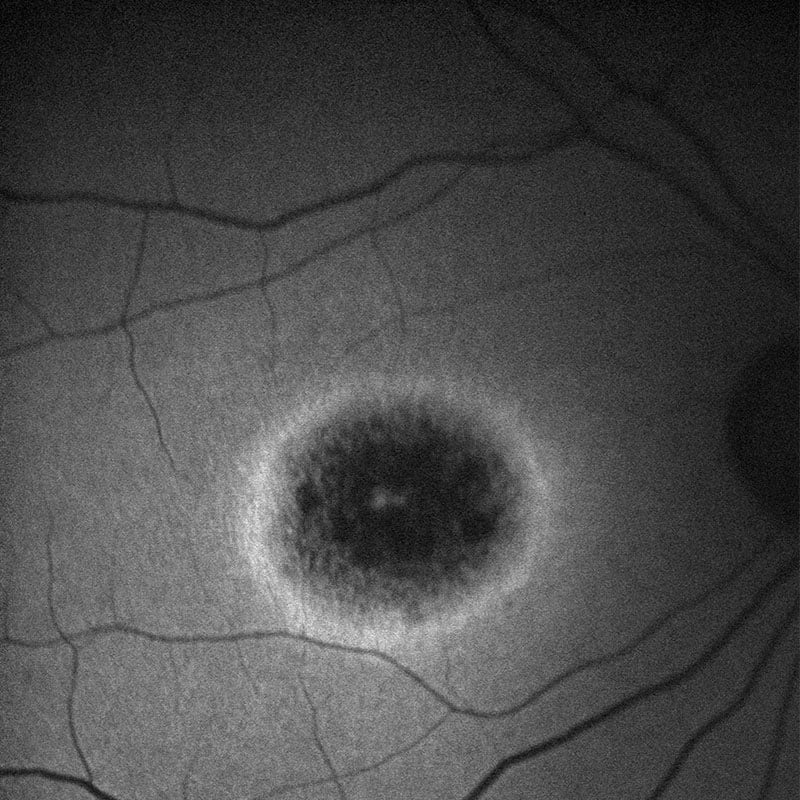

Η μελαγχρωστική αμφιβληστροειδοπάθεια είναι η πιο συχνή από τις δυστροφίες του αμφιβληστροειδή. Ουσιαστικά είναι ομάδα παθήσεων με ποικιλία στα χαρακτηριστικά και τη βαρύτητα της νόσου αλλά με κοινό γνώρισμα τη δυσκολία στη νυχτερινή όραση (νυκταλωπία) και τη δυσλειτουργία η οποία ξεκινάει από το επίπεδο των ραβδίων (κυττάρων του αμφιβληστροειδή – φωτοϋποδοχέων – τα οποία είναι υπεύθυνα για τη νυχτερινή και την περιφερική μας όραση). Πολλοί ασθενείς διατηρούν, ωστόσο, την κεντρική τους όραση μέχρι προχωρημένη ηλικία. Η κλινική διάγνωση της πάθησης γίνεται με τη συσχέτιση του ιστορικού, του κλινικού και απεικονιστικού ελέγχου καθώς και της Ηλεκτροφυσιολογικής μελέτης (Ηλεκτροαμφιβληστροειδογράφημα). Η γενετική διάγνωση της πάθησης απαιτεί τον γενετικό έλεγχο